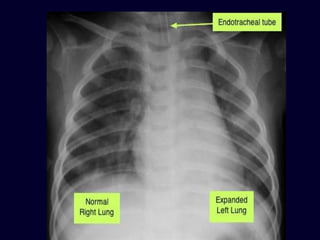

Radiographs are obtained

routinely after intubation

Endotracheal tube

• (ETT) is

recognized by

thin white opaque

line usually

running the

length of the tube

• A correctly

positioned

ETT lies in the

mid trachea and

its tip is

approximately 4-

5 cm above the

carina

3-4 cm

• the tip of the ETT is

low lying and is at

the origin of the

right main

bronchus. Further

migration of the

ETT will result in

right sided

endobronchial

intubation and

collapse of the left

lung

Radiographs are obtained routinely after intubation

Endotracheal tube (ETT) is recognized by thin white

opaque line usually running the length of the tube

 Tip of

(red arrow)

projects below the

carina (blue

arrow) into the

bronchus

intermediacy on

the right